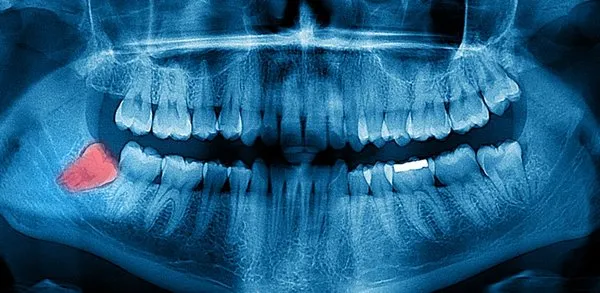

Cyst Formation:

One of the biggest problems caused by wisdom teeth is cyst formation. In order to prevent the formation of cysts that cause problems such as deterioration of the jaw structure, bone damage and tooth deterioration, the wisdom tooth must be removed with the help of a specialist physician.